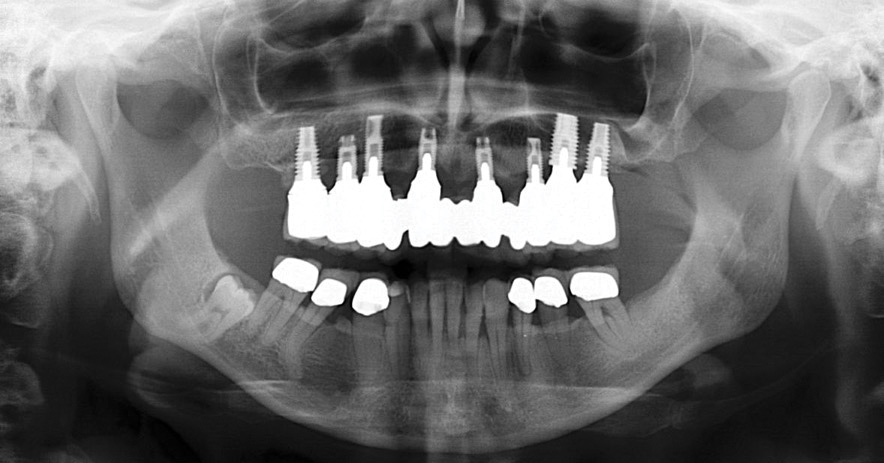

For patients in whom alveolar bone is present in all three zones of the edentulous maxilla, conventional implants may be placed (Figure 5). This should allow for a favorable arch form of anterior, posterior, and possibly intermediate implants for a fixed prosthesis.8,9

Fig 5. Axial implant placement, with presence of bone in zones 1, 2, and 3.

Figure 5